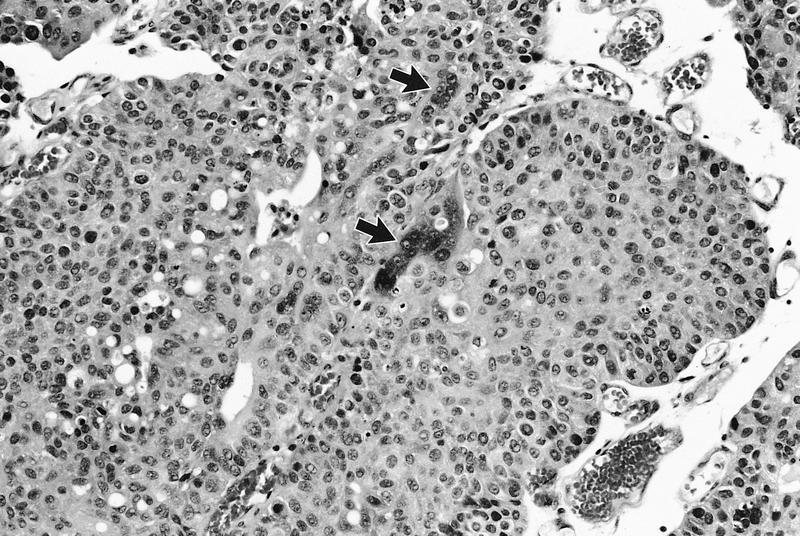

- Wide spectrum of trophoblastic differentiation, ranging from scattered isolated cells with trophoblastic differentiation to pure choriocarcinoma

- Often admixed with conventional urothelial carcinoma or other variants / subtypes

- When present as scattered isolated cells, they can be in the form of cytotrophoblasts (usually indistinguishable from high grade urothelial carcinoma or syncytiotrophoblast (recognizable by their multinucleated giant cells)

- Resembles choriocarcinoma in other organs

Microscopic (histologic) images